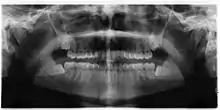

| Impacted wisdom teeth | |

| 3D CT of an impacted wisdom tooth adjacent the inferior alveolar nerve prior to removal of wisdom tooth | |

| Diagnostic method | Examination, x-ray |

Impacted wisdom teeth are classified by their direction of impaction, their depth compared to the biting surface of adjacent teeth and the amount of the tooth's crown that extends through gum tissue or bone. Impacted wisdom teeth can also be classified by the presence or absence of symptoms and disease. Screening for the presence of wisdom teeth often begins in late adolescence when a partially developed tooth may become impacted. Screening commonly includes a clinical examination as well as x-rays such as panoramic radiographs.

If the tooth cannot be assessed with clinical exam alone, the diagnosis is made using either a panoramic radiograph or cone-beam CT. Where unerupted wisdom teeth still have eruption potential several predictors are used to determine the chance of the teeth becoming impacted. The ratio of space between the tooth crown length and the amount of space available, the angle of the teeth compared to the other teeth are the two most commonly used predictors, with the space ratio being the most accurate. Despite the capacity for movement into early adulthood, the likelihood that the tooth will become impacted can be predicted when the ratio of space available to the length of the crown of the tooth is under 1.[5]: 141